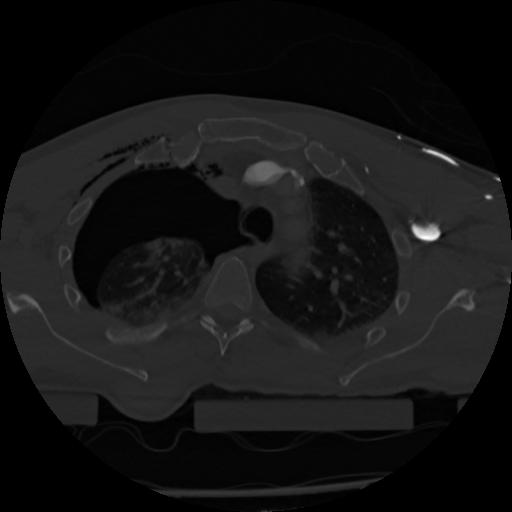

22 ANGIO,CE,Vol,0.5,ANGIO,,